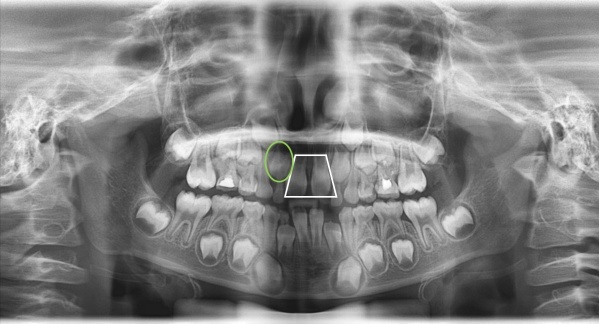

一般孩子的門牙是個(ge) 萌出後,但是基本外形比較大,所以萌出後,旁邊的側(ce) 切牙也想要萌出,但是一次縫隙往往不夠,所以側(ce) 切牙的就會(hui) 對門牙牙根造成擠壓,導致門牙就像是蹺蹺板一樣,牙根被擠到在中間,但是長出來的部分被擠到兩(liang) 邊了,所以出現了間隙。